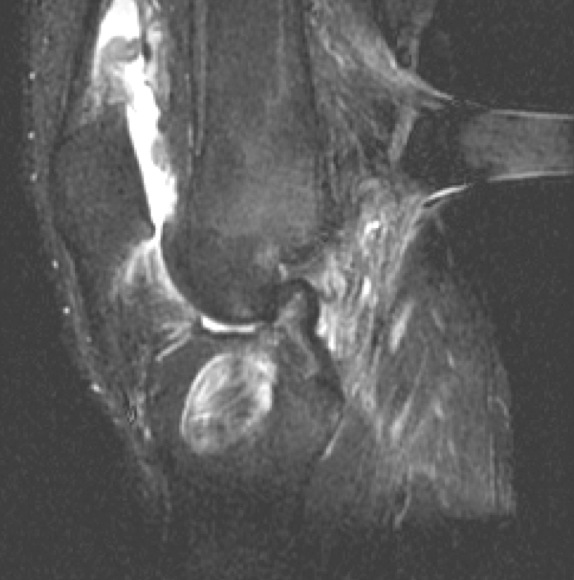

Figure 1 for case ACL graft complications

Figure 1

Ganglion with chronic graft tear, chronic roof impingement, anteriorly placed tibial tunnel

Diagnosis

ACL graft complications